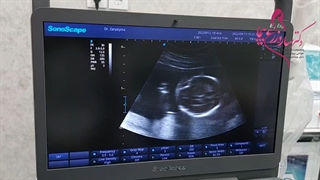

پخش صدا بی اختیاری ادراری اشتراکگذاری لیست پخش ۰ نظر ۰ نظر دانلود دانلود ویدیو دانلود کیفیت 1080p ۲۸.۲۲ مگابایت دانلود کیفیت 720p ۱۵.۰۷ مگابایت دانلود کیفیت 480p ۹.۵۵ مگابایت دانلود کیفیت 360p ۶.۸۴ مگابایت دانلود کیفیت 240p ۴.۲۳ مگابایت دانلود کیفیت 144p ۲.۶۵ مگابایت گزارش تخلف بیشتر گزینههای بیشتر لیست پخش لایکها گزارش تخلف ۱ لایک دکتر ساره زرع پیما منتشر شده در تاریخ ۱۴۰۱/۰۵/۰۴ این کانال دنبال شد دنبال کردهاید دنبال کردن این کانال دنبال کردن دکتر ساره زرع پیما جراح و متخصص زنان و زایمان جراح زیبایی زنان ادامه نظرات لبخند لبخند لغو ثبت نظری برای نمایش وجود ندارد.